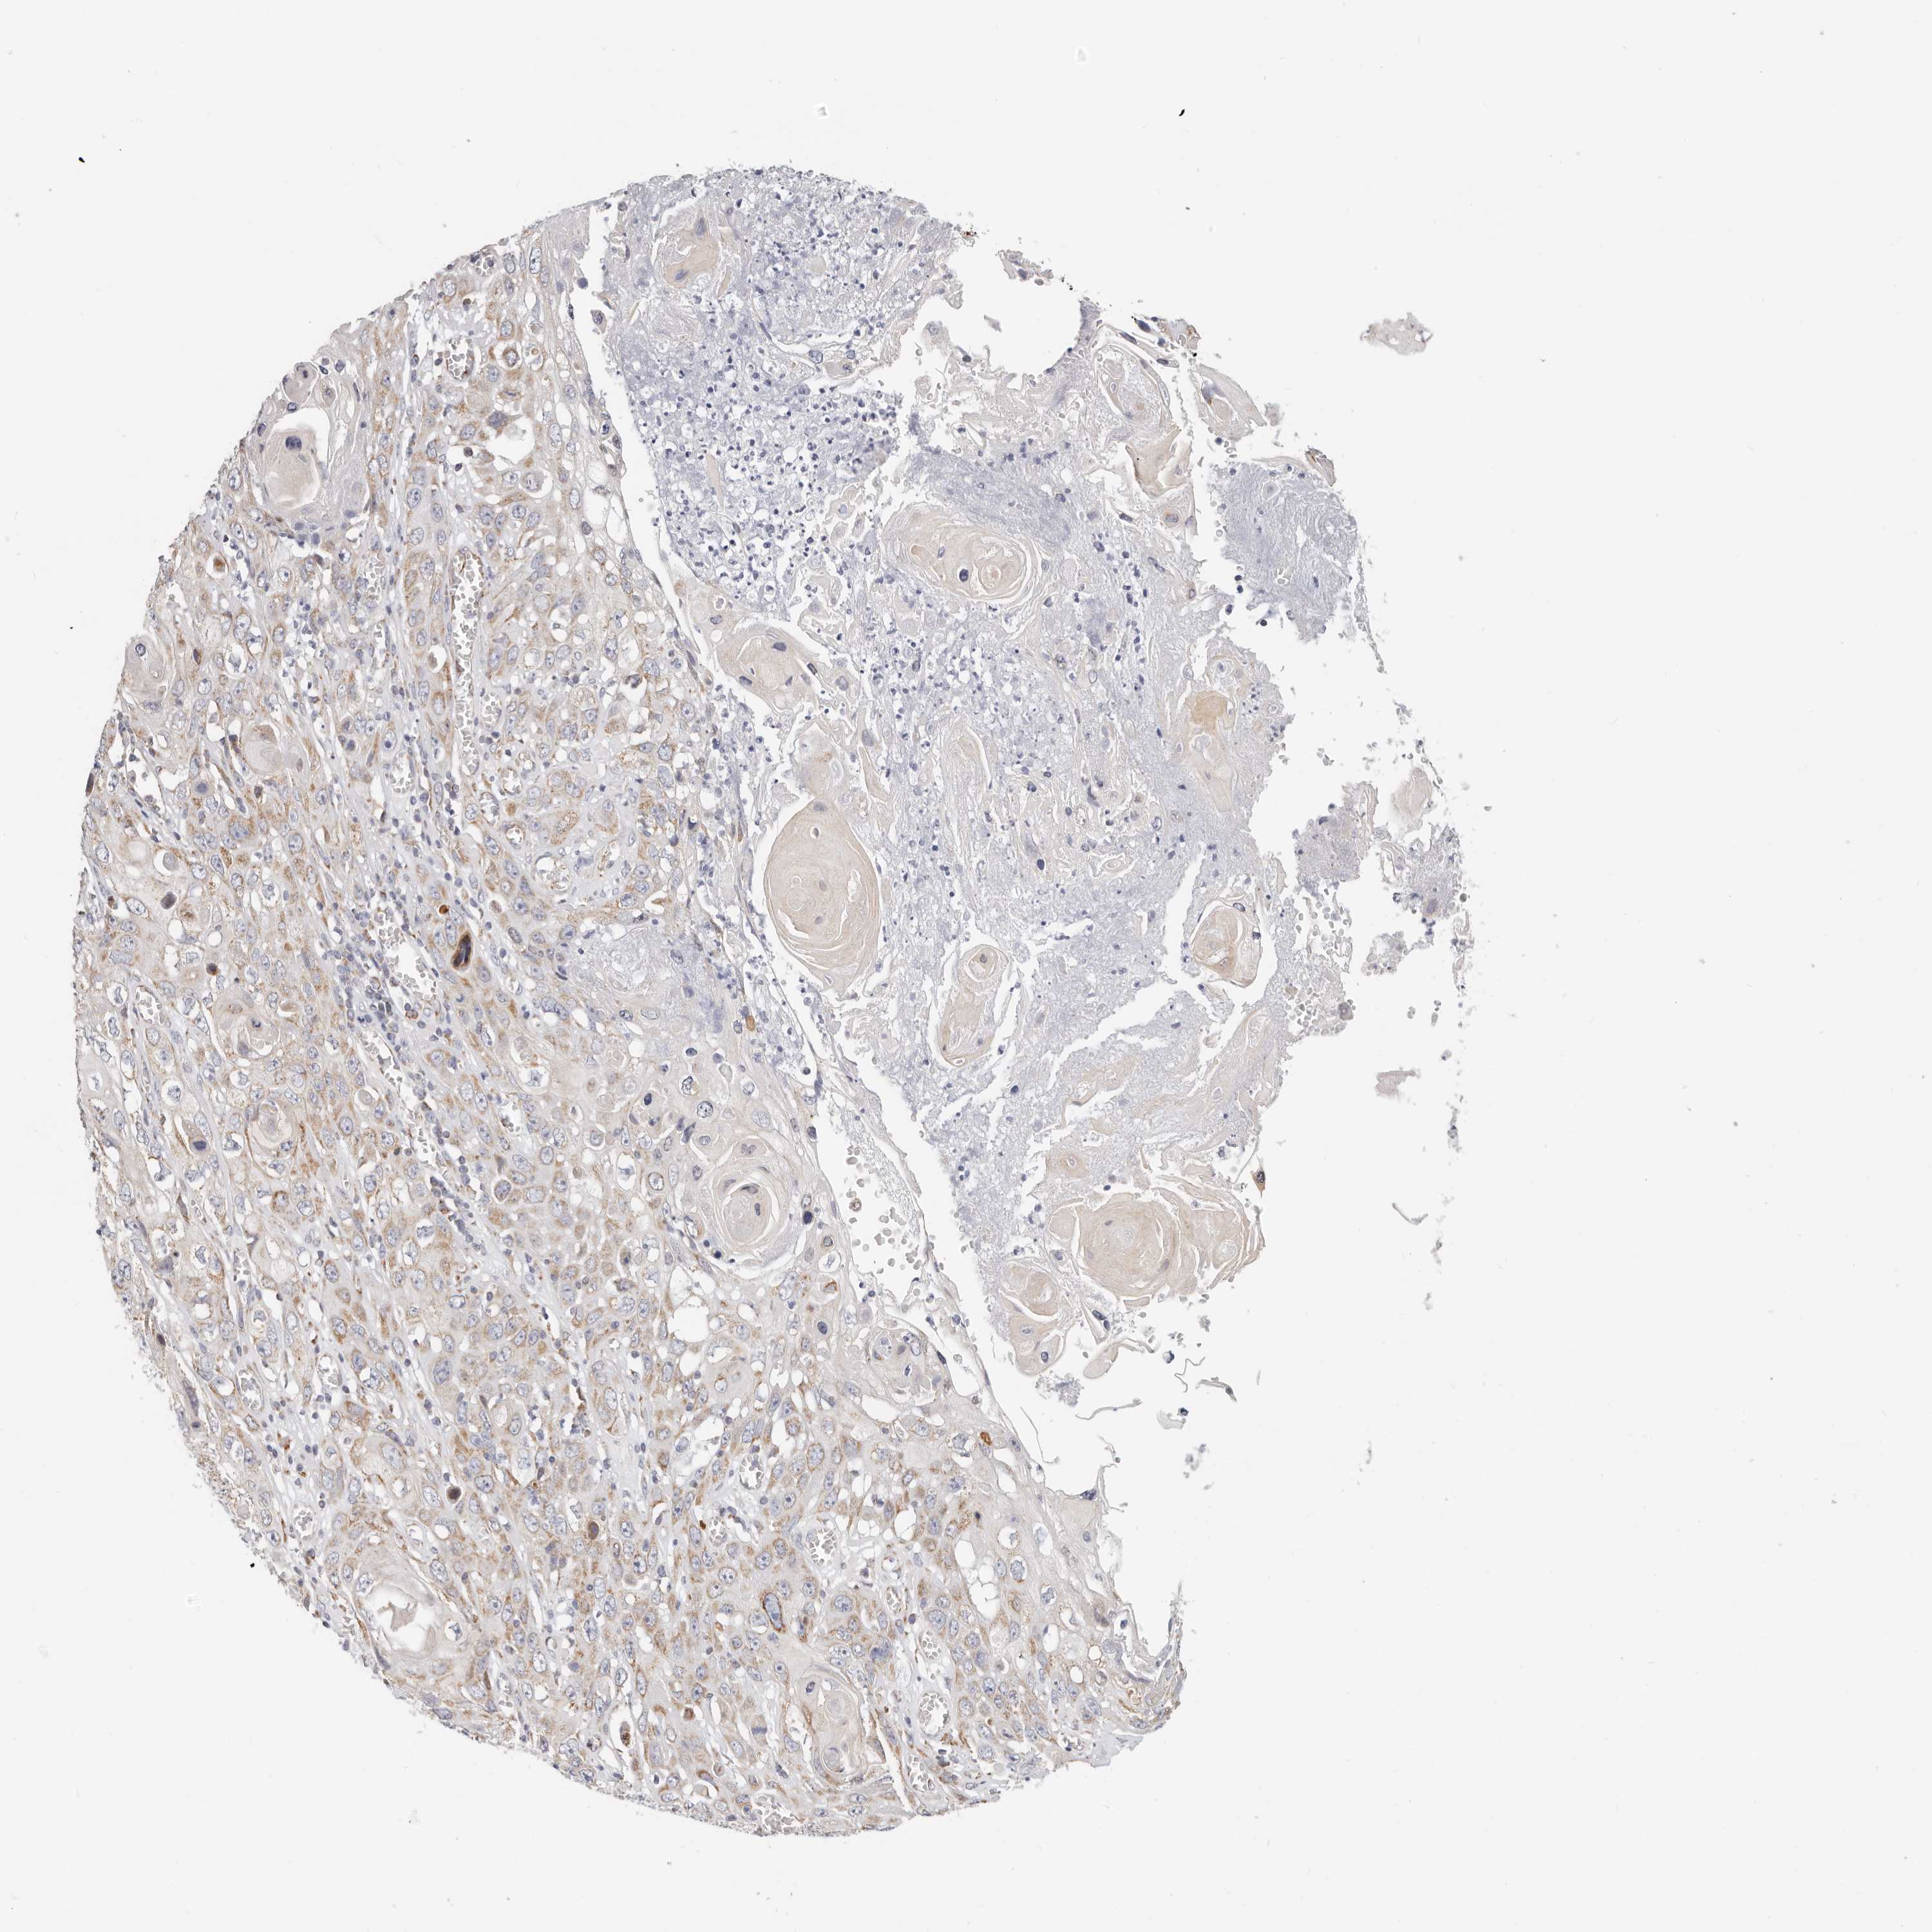

SKIN CANCER - Protein expressioni

A mouse-over function shows sample information and annotation data. Click on an image to view it in a full screen mode. Samples can be filtered based on level of antibody staining by selecting one or several of the following categories: high, medium, low and not detected. The assay and annotation is described here.

Each image is clickable and will lead to virtual microscopy that enables deeper exploration of all samples and also displays staining intensity scores, fraction scores and subcellular localization as well as patient and tissue information for each sample.

HPA030212

HPA030213

HPA030214

HPA030215

CAB013496

Staining

High

Medium

Low

Not detected

Intensity

Strong

Moderate

Weak

Negative

Quantity

>75%

75%-25%

<25%

None

Location

Nuclear

Cytoplasmic/membranous

Cytoplasmic/membranous,nuclear

Basal cell carcinoma

Squamous cell carcinoma, NOS

Squamous cell carcinoma, metastatic, NOS

Adnexal tumor, benign